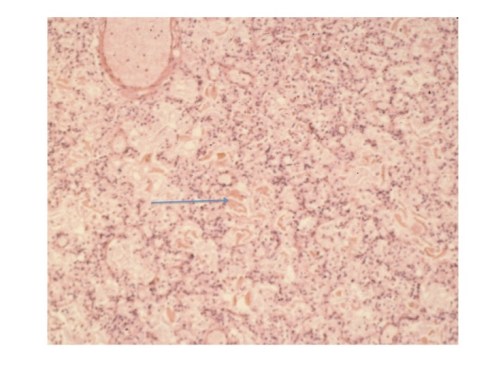

Even sterile meconium might be expected to elicit acute inflammation in the lung since it would be expected to have bile and digestive enzymes that could cause tissue damage. Naturally, meconium in the colon does not elicit inflammation, but this lack can be attributed to a specialized mucosa. More telling is the frequent lack of inflammation in fetal membranes with pigment macrophages that are evidence of deep penetration of meconium. Yet even here it could be argued that the lack of vascularity and the effectiveness of the macrophages prevent inflammation. The presence of meconium in the lung of stillborn infants without inflammation does not prove that given more time before death that tissue injury would not have occurred. Yet some autopsies of neonates also demonstrate meconium without inflammation (Fig 1). Despite some experimental evidence of lung injury, the human pathologic evidence is against significant tissue damage from aspirated meconium.

Fig 1: The arrow points to pigmented protein in the airway of an infant who rupture of membranes with thick meconium for 12 hours prior to delivery. At delivery he had severe arthrogryposis and pulmonary hypoplasia and could not be resuscitated. The airways are full of meconium without inflammation. (H&E, 40x)